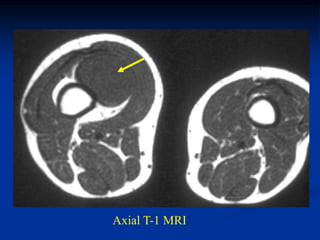

CLASSIC Case #279 Sagittal T-1 MRI 63 year female with myxolipoma knee

• 121.